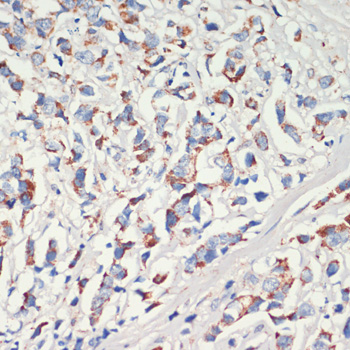

DescriptionAFG3L2 Polyclonal Antibody. Unconjugated. Raised in: Rabbit.

ApplicationWB, IHC, IP